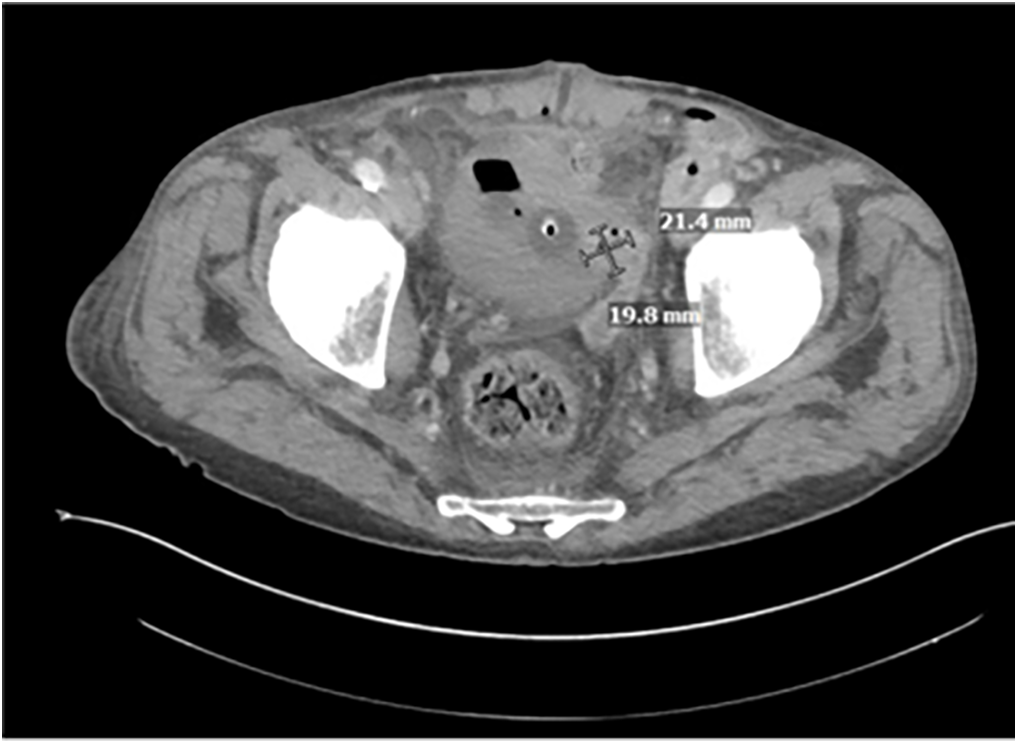

On hospital day four, a repeat CT scan revealed an interval decrease in the sizes of the various pelvic abscesses. There was a new, tiny focus of gas within the bladder along the left lateral wall adjacent to the left vas deferens, highly suspicious for a developing fistula (Figure 2).

FIGURE 2. Repeat CT A/P with IV contrast on hospital day #4